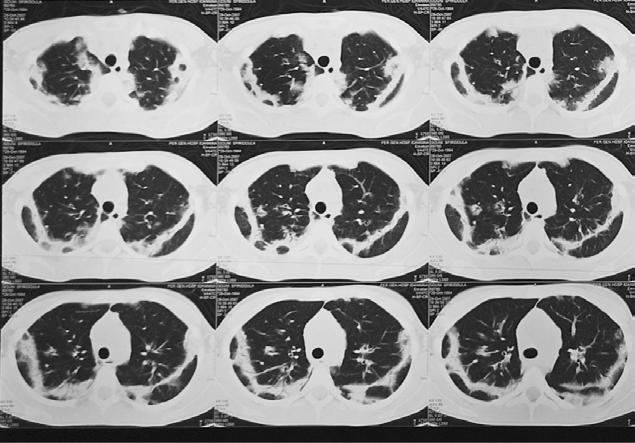

Eosinophilia and Pulmonary infiltrates as a first sign of Primary Hypereosinophilic Syndrome in a 13,5 years old girl

Ανάλογα με τον απόλυτο αριθμό των ηωσινοφίλων, χαρακτηρίζεται ως ήπια, μέτρια ή σοβαρή. Παρουσιάζεται η περίπτωση κοριτσιού 13.5 ετών, που προσκομίστηκε με πυρετό, αίσθημα κόπωσης, βήχα, κοιλιακό άλγος και σοβαρού βαθμού ηωσινοφιλία και πνευμονικά διηθήματα. Επιχειρείται βήμα - βήμα η διαγνωστική προσπέλαση του περιστατικού, παρατίθεται ο

λεπτομερής εργαστηριακός και παρακλινικός έλεγχος, η πορεία της νόσου μέχρι να τεθεί η τελική διάγνωση, αυτή του Ιδιοπαθούς Υπερηωσινοφιλικού Συνδρόμου, καθώς και η θεραπευτική της αντιμετώπιση.

Λέξεις-κλειδιά: ηωσινοφιλία, πνευμονικά διηθήματα, ιδιοπαθές υπερηωσινοφιλικό